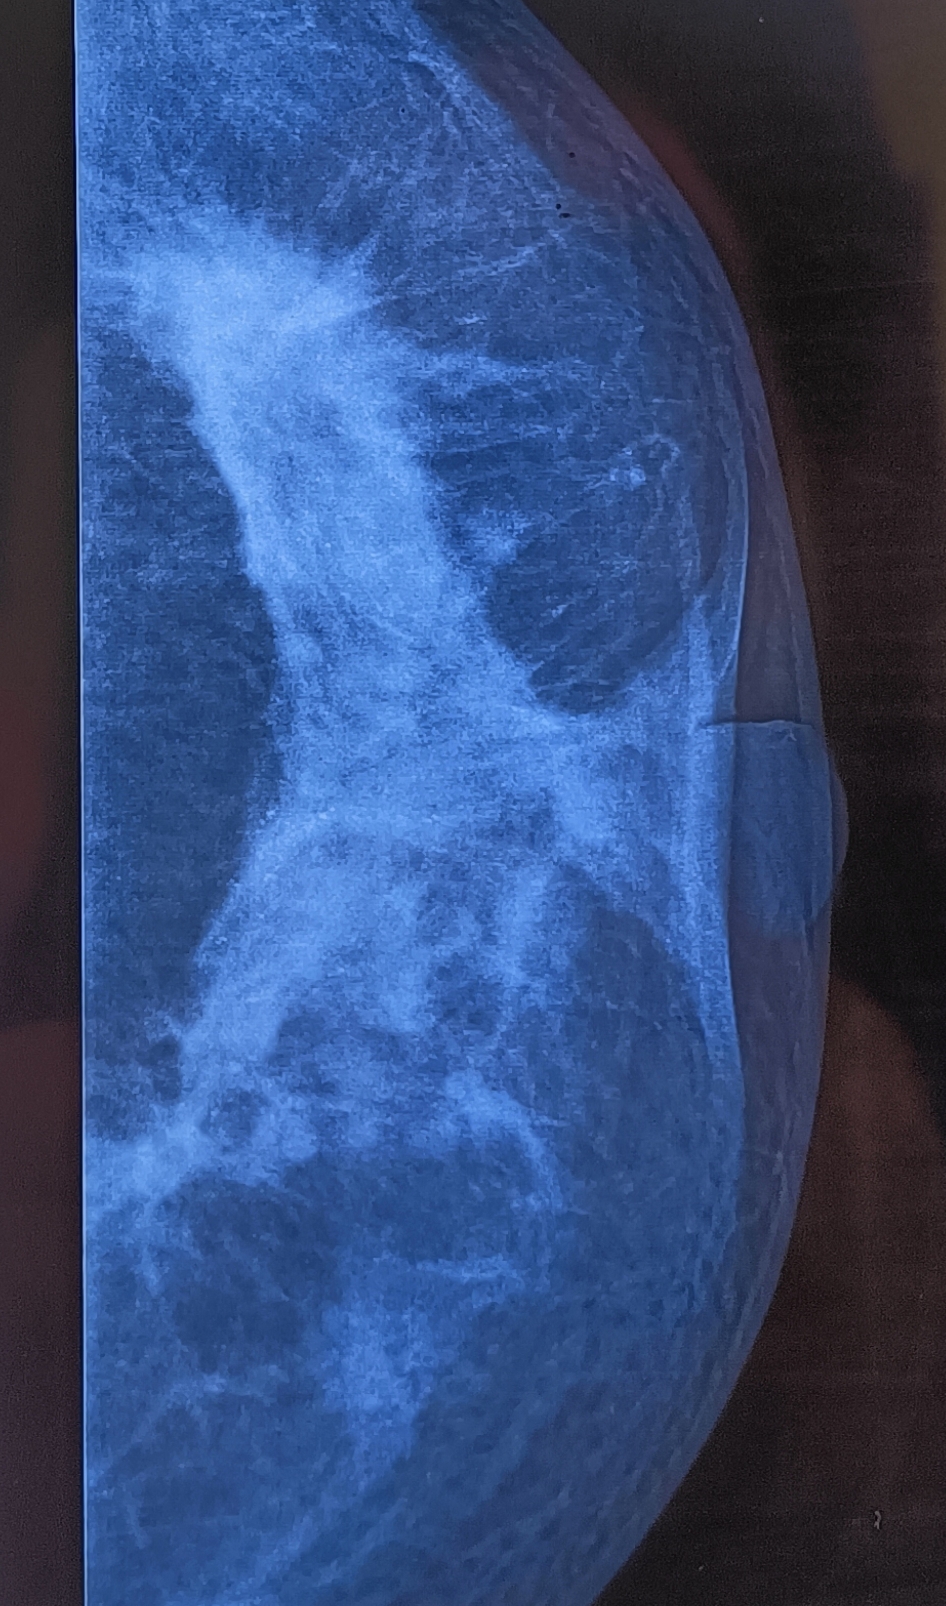

A 42 years old female from Chouhat presented with undiagnosed firmness of the breast which she had noted. Her mother had earlier been treated for breast cancer in our unit more than 25 years earlier. On examination, the nipple retraction was obvious, but FNAC had reported no malignancy. This was perhaps because on palpation no discrete hard mass (as one would find typically) was palpable and so the needle missed the target.